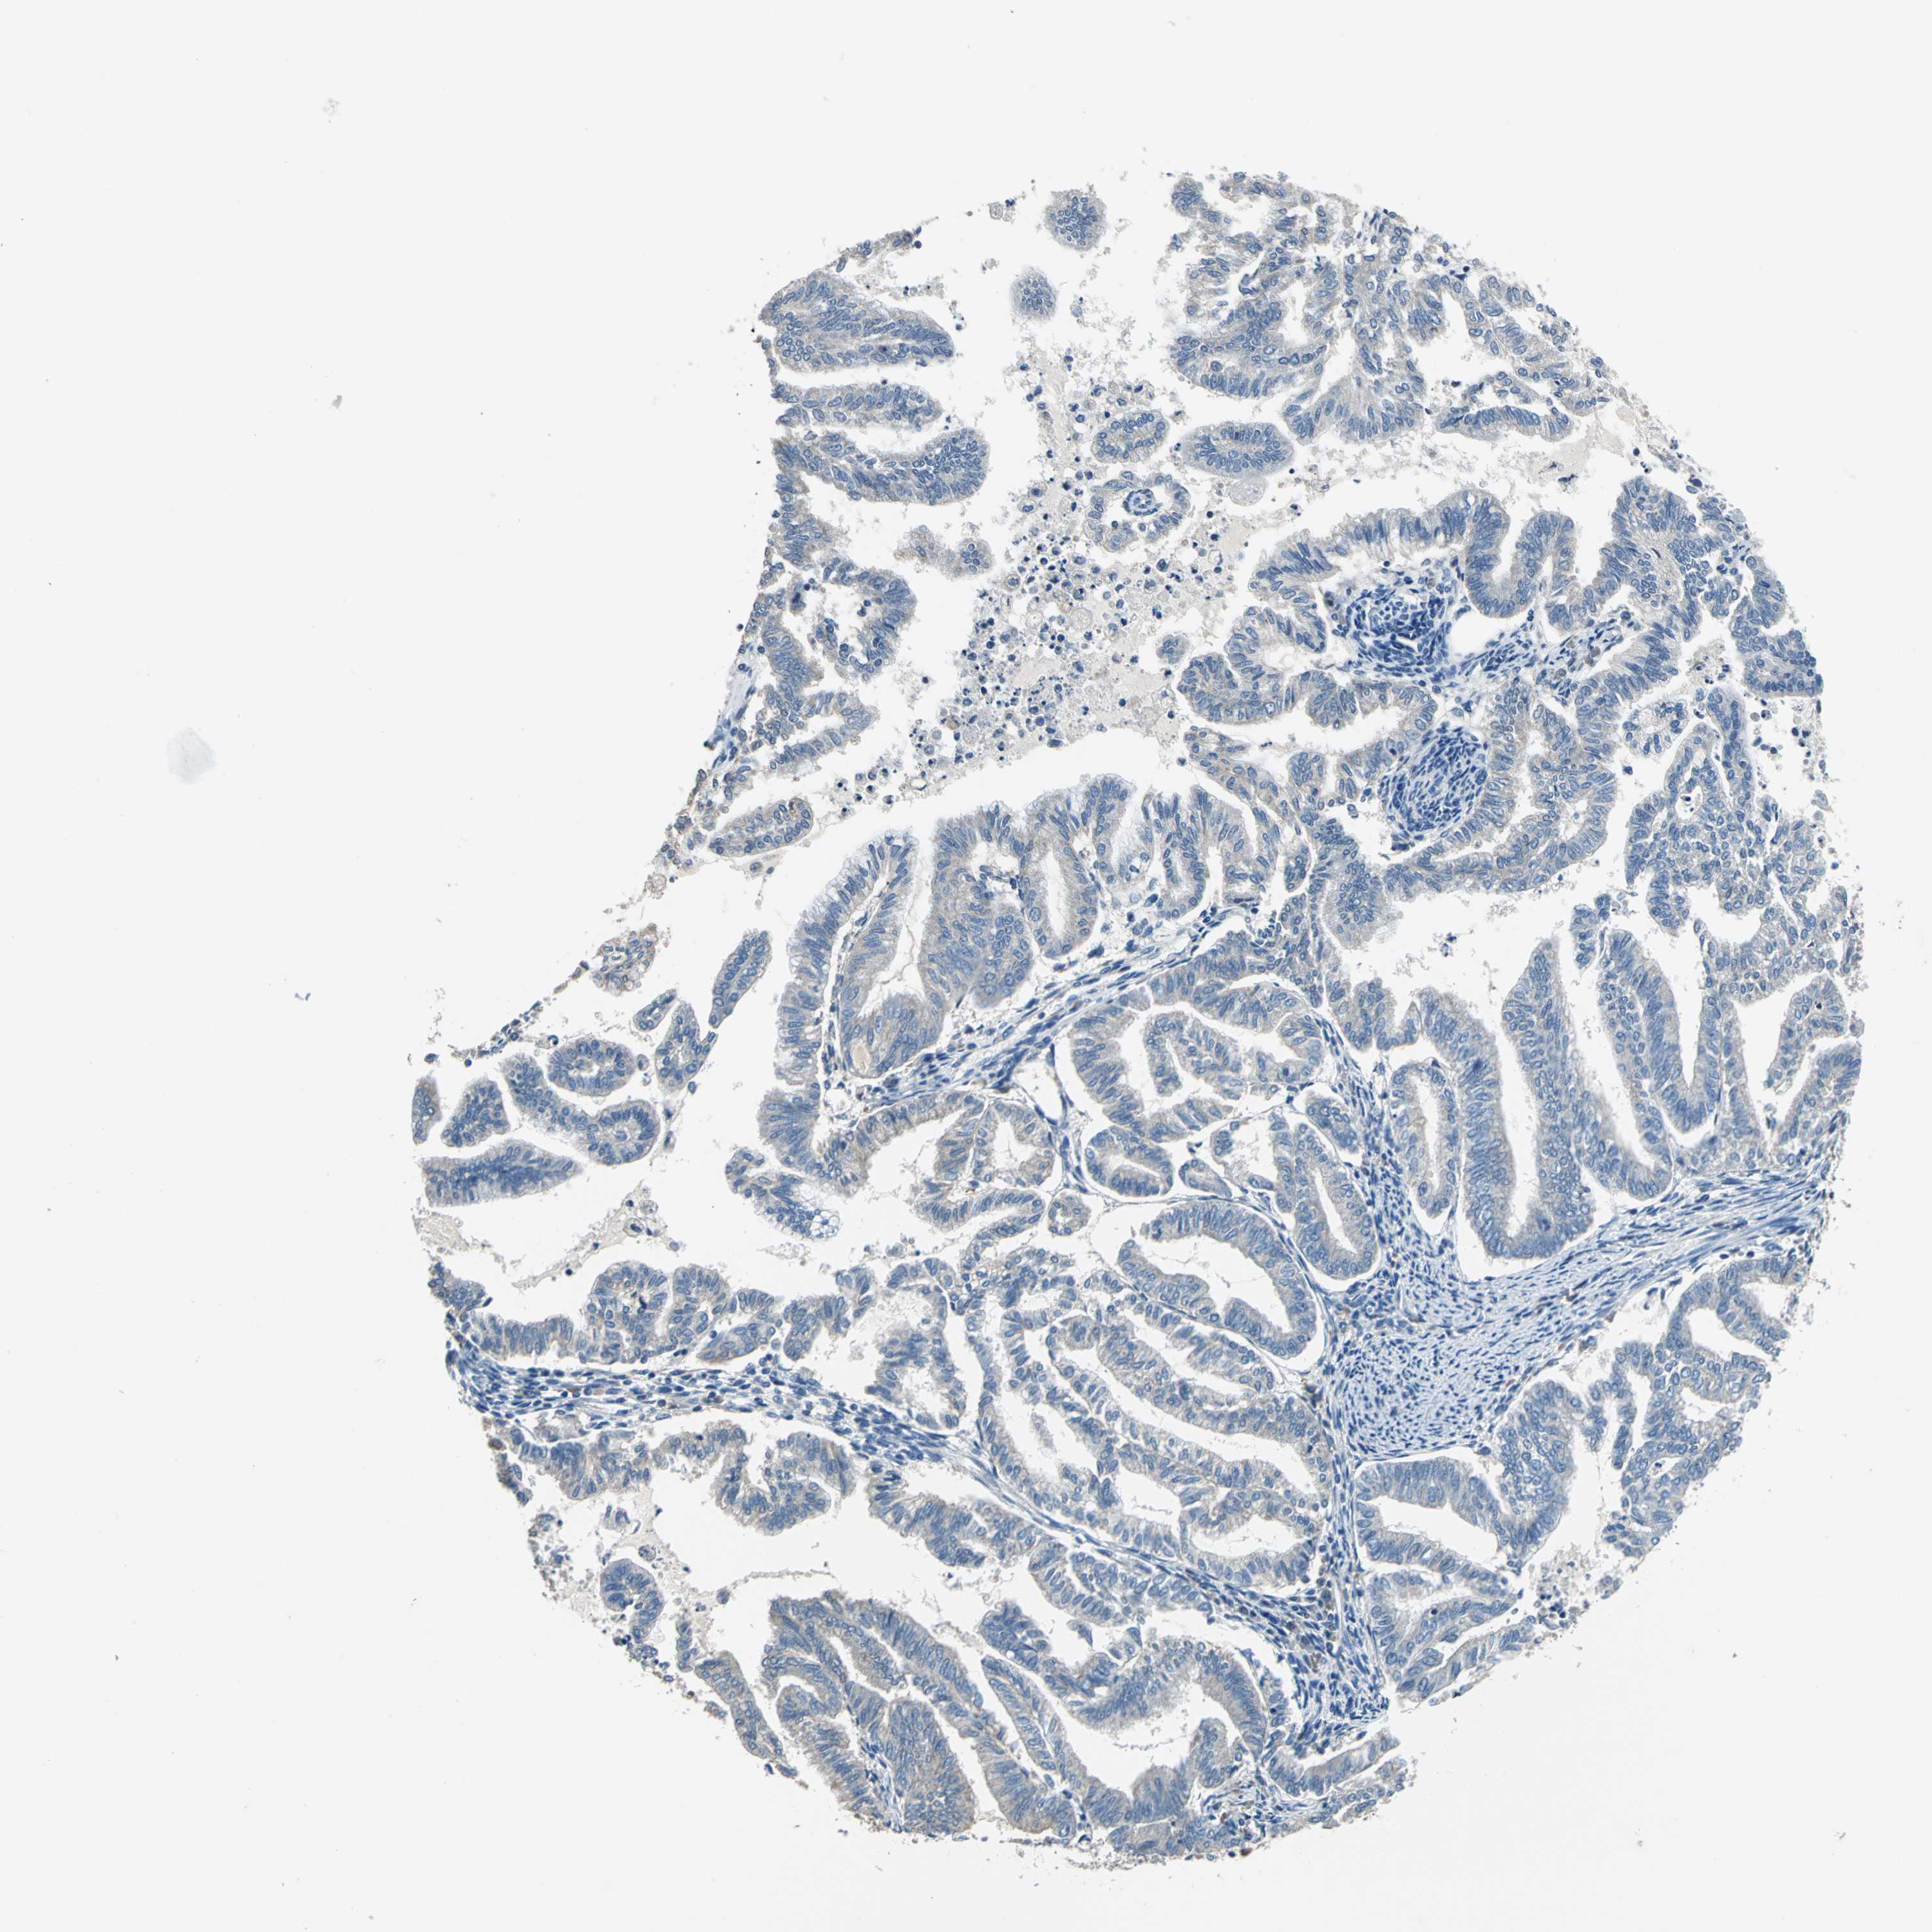

ENDOMETRIAL CANCER - Protein expressioni

A mouse-over function shows sample information and annotation data. Click on an image to view it in a full screen mode. Samples can be filtered based on level of antibody staining by selecting one or several of the following categories: high, medium, low and not detected. The assay and annotation is described here.

Note that samples used for immunohistochemistry by the Human Protein Atlas do not correspond to samples in the TCGA dataset.

Antibody stainingi

Antibody staining in the annotated cell types in the current human tissue is reported as not detected, low, medium, or high, based on conventional immunohistochemistry profiling in selected tissues. This score is based on the combination of the staining intensity and fraction of stained cells.

Each image is clickable and will lead to virtual microscopy that enables deeper exploration of all samples and also displays staining intensity scores, fraction scores and subcellular localization as well as patient and tissue information for each sample.

Antibody HPA006563

Antibody HPA006564

Antibody CAB003844

Antibody CAB016290